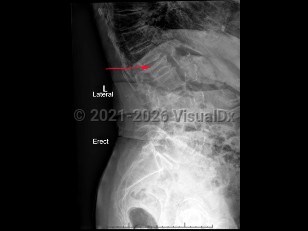

Osteoporotic vertebral compression fracture

Spondylolysis

Spondylolisthesis

Lumbar spinal stenosis